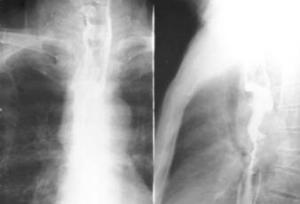

食道癌是发生在食管上皮组织的恶性肿瘤,占所有恶性肿瘤的2%。全世界每年约有22万人死于食道癌,我国是食道癌高发区,因食道癌死亡者仅次于胃癌居第二位,发病年龄多在40岁以上,男性多于女性,但近年来40岁以下发病者有增长趋势。食道癌的发生与亚硝胺慢性刺激、炎症与创伤,遗传因素以及饮水、粮食和蔬菜中的微量元素含量有关。[1]